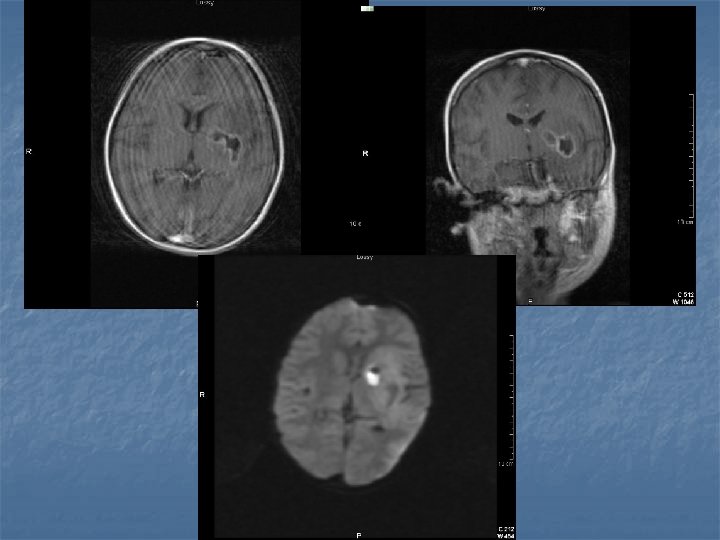

Toxoplasmosis n n n Yer kaplayan lezyonların % 60’ı % 30 olguda mevcut Kortikomedüller bileşke (? ), basal ganglion ve talamusda sık tutulum BT-MR. . . >5 lezyon, halka tarzında kontrast (+), nodüler, ödem ve kitle etkisi Erken tanı önemli. . . tedavi edilebilir 2 hafta primethamine+sulfadiazine

Biopsi n n n % 96 olguda tanı koydurucu Mortalite % 0 Majör morbidite % 2 Minör morbidite % 3 -4 Farklı çalışmalarda. . . farklı algoritmler Genel yaklaşım: Radyolojik olarak tanı konulabilen olgularda antitoxo ted. . . .